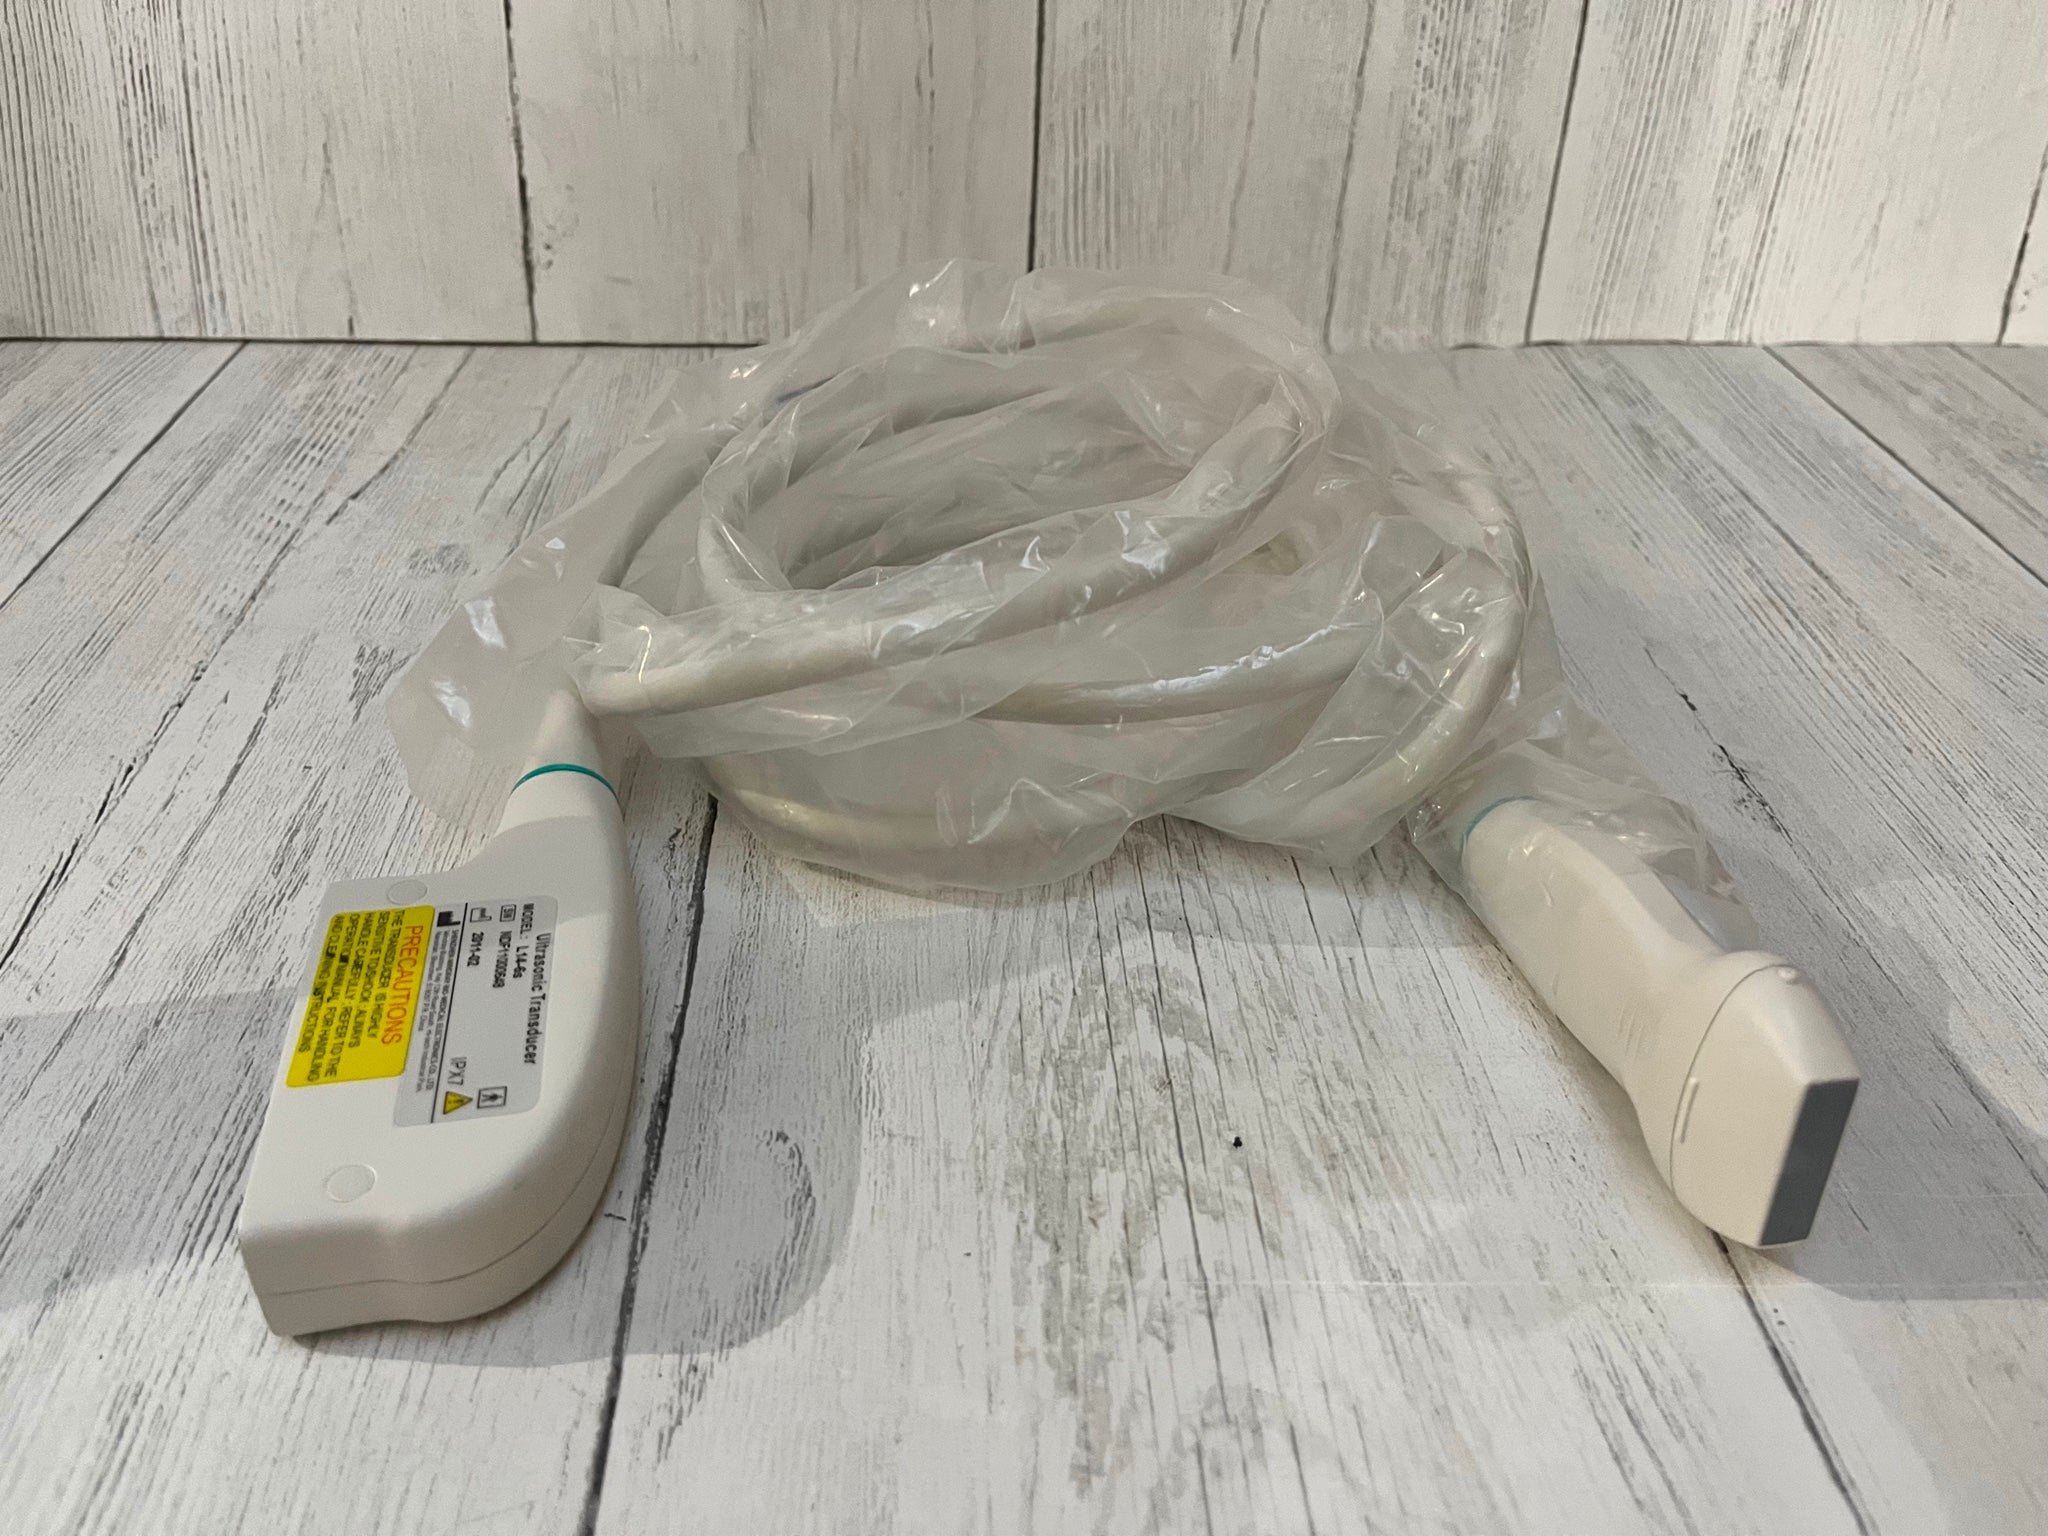

Probe Function: 3.5MHZ convex, abdominal organs

Probe 2: 7.5MHZ Transvaginal probe:gynecologic examination

The Diagnostic Ultrasound Scanner utilizes state-of-the-art B Mode technology to produce high-quality images. This feature allows healthcare professionals to visualize internal structures clearly, aiding in accurate diagnoses. Because it combines both convex and transvaginal probes, the scanner is versatile and suitable for various examinations, making it ideal for hospitals and clinics alike.